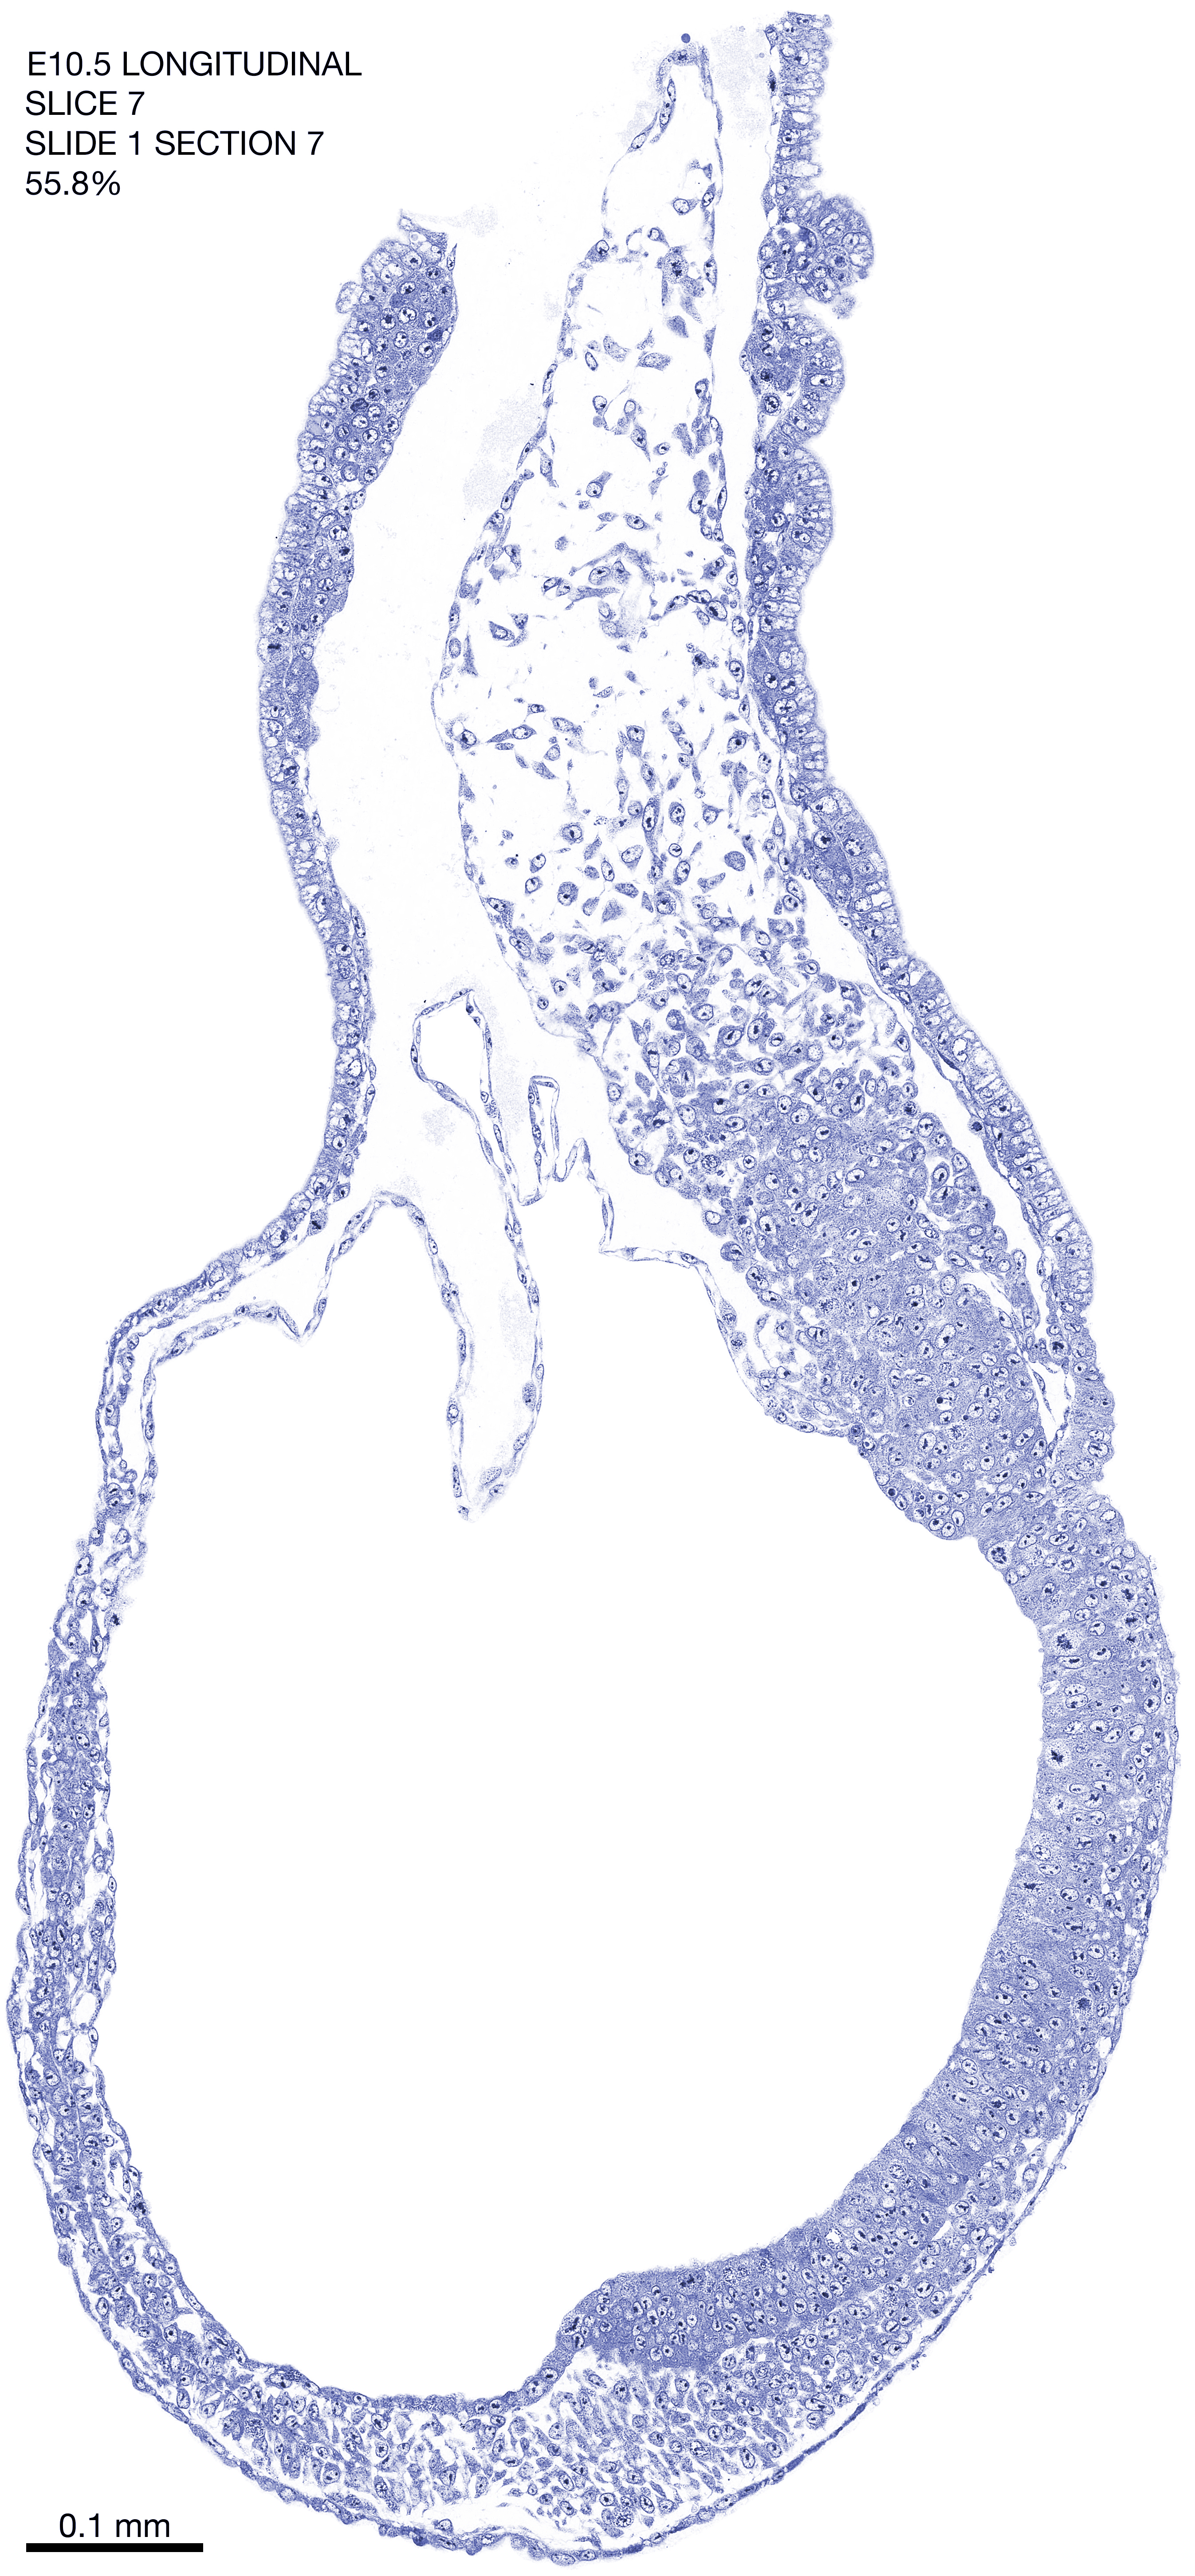

E10.5 Longitudianal Archive This page contains jpg files of ALL SLICES (each 3µm thick) that were scanned of the E10.5 longitudinally cut specimen. Download: Large | High Res Download: Large | High Res Download: Large | High Res Download: Large | High Res Download: Large | High Res Download: Large | High Res Download: Large | High Res Download: Large | High Res Download: Large | High Res Download: Large | High Res Download: Large | High Res Download: Large | High Res Download: Large | High Res Download: Large | High Res Download: Large | High Res Download: Large | High Res Download: Large | High Res Download: Large | High Res Download: Large | High Res Download: Large | High Res Download: Large | High Res Download: Large | High Res Download: Large | High Res Download: Large | High Res Download: Large | High Res Download: Large | High Res Download: Large | High Res Download: Large | High Res Download: Large | High Res Download: Large | High Res Download: Large | High Res Download: Large | High Res Download: Large | High Res Download: Large | High Res Download: Large | High Res Download: Large | High Res Download: Large | High Res Download: Large | High Res Download: Large | High Res Download: Large | High Res Download: Large | High Res Download: Large | High Res Download: Large | High Res Download: Large | High Res Download: Large | High Res Download: Large | High Res Download: Large | High Res Download: Large | High Res Download: Large | High Res Download: Large | High Res Download: Large | High Res Download: Large | High Res Download: Large | High Res Download: Large | High Res Download: Large | High Res Download: Large | High Res Download: Large | High Res Download: Large | High Res